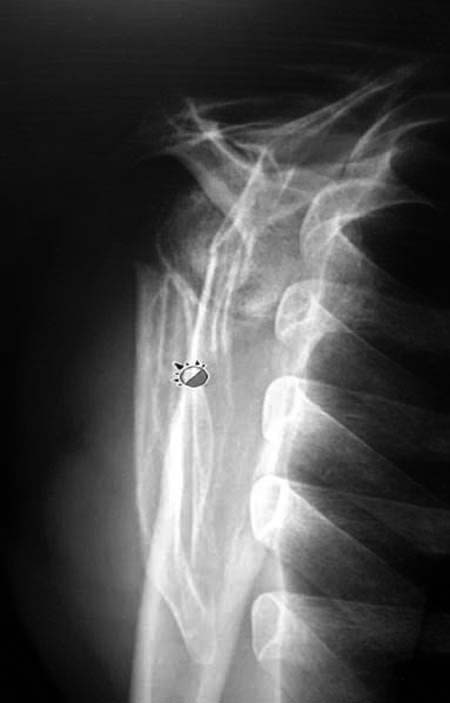

Данный перелом относится к перелому тело лопатки и несмотря на

наслоение, где лопатка покрывает грудную клетку, но можно увидеть три

большие фрагмента, которые находятся в разных плоскостях. Суставная

поверхность расположена намного медиальнее, что нарушает бланс мышц,

которая в последующем может привести к ограничению движения верхного

пояса. Расположение суставной поверхности нуждается в уточнении

дополнительными исследованиями, включая КТ и стандартные снимки плеча.!